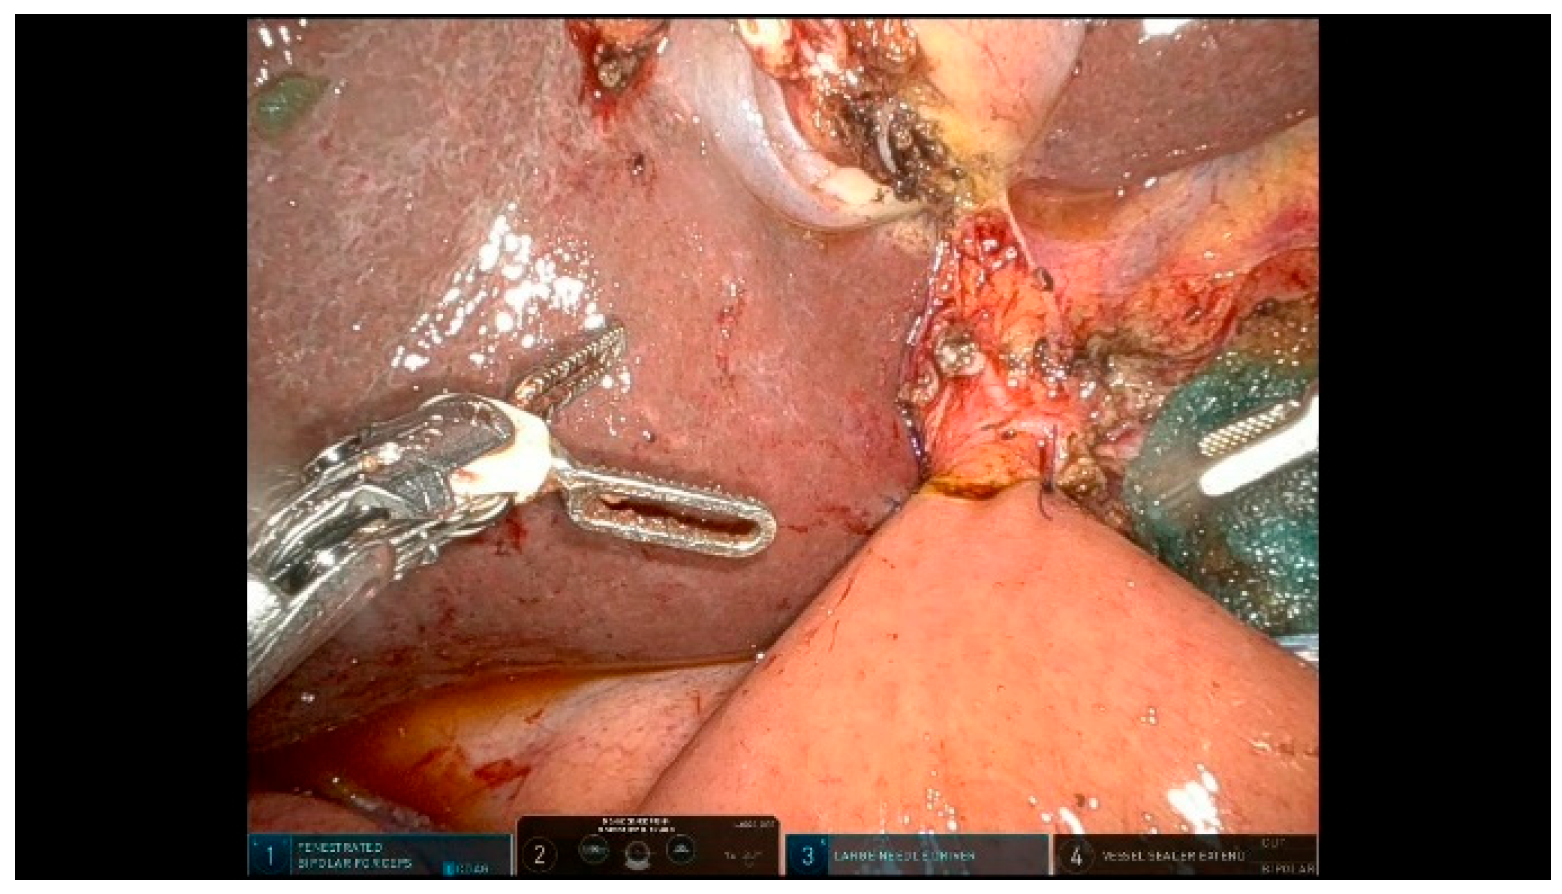

3.2.2. Step 12: Hepaticojejunostomy